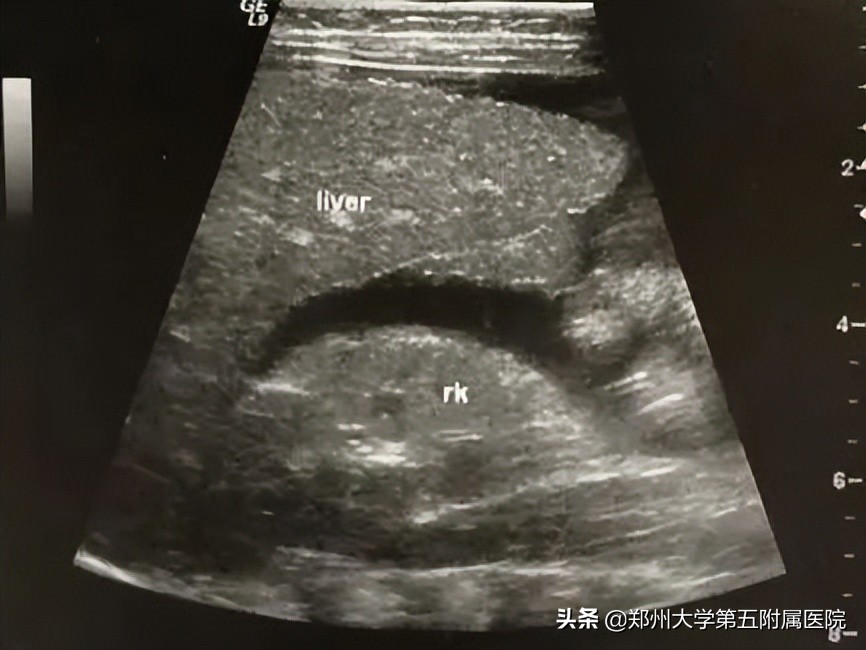

胆道闭锁 患儿生后即出现黄疸、进行性加重、皮肤巩膜黄染、面色暗黄、大便淡黄色或白色陶土样等症状。由于新生儿胆总管纤细难以观察,因此通过以下胆囊形态变化判断是否胆道梗阻: 胆囊大小正常但形态僵硬 (图2),边缘不光整,长度可达2-3cm,内径大于0.4cm,可有小的憩室样结构形成; 小胆囊 ,长度小于1-1.5cm,内径0.2cm,充盈差; 胆囊小而且无充盈,仅可见胆囊痕迹,喂奶后无变化 ;以上三种胆囊均可合并有 胆总管区囊肿,可与胆囊管及胆囊相通 ,但 与肝左、右管不相通 (见图3); 小部分病例 可见到 肝内胆管局限性扩张 (图4);病程后期(3个月以上),显示肝硬化改变(图5)。

▲ 图4